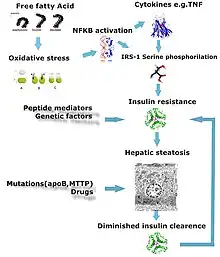

Defects in fatty acid metabolism are responsible for pathogenesis of FLD, which may be due to imbalance in energy consumption and its combustion, resulting in lipid storage, or can be a consequence of peripheral resistance to insulin, whereby the transport of fatty acids from adipose tissue to the liver is increased.[13][22] Impairment or inhibition of receptor molecules (PPAR-α, PPAR-γ and SREBP1) that control the enzymes responsible for the oxidation and synthesis of fatty acids appears to contribute to fat accumulation. In addition, alcohol use disorder is known to damage mitochondria and other cellular structures, further impairing cellular energy mechanism. On the other hand, non-alcoholic FLD may begin as excess of unmetabolised energy in liver cells. Hepatic steatosis is considered reversible and to some extent nonprogressive if the underlying cause is reduced or removed.

Severe fatty liver is sometimes accompanied by inflammation, a situation referred to as steatohepatitis. Progression to alcoholic steatohepatitis (ASH) or non-alcoholic steatohepatitis (NASH) depends on the persistence or severity of the inciting cause. Pathological lesions in both conditions are similar. However, the extent of inflammatory response varies widely and does not always correlate with degree of fat accumulation. Steatosis (retention of lipid) and onset of steatohepatitis may represent successive stages in FLD progression.[23]